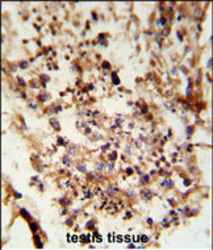

Immunohistochemistry

GTX80576 IHC

Method: